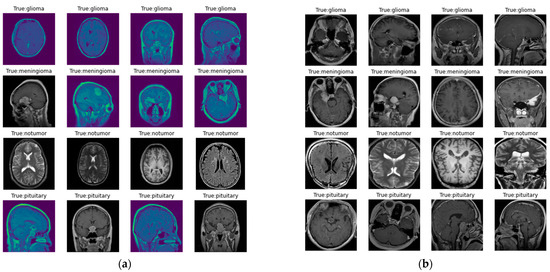

The images in the dataset are represented in Figure 2, where Figure 2a represents the original image, and Figure 2b represents the image following preprocessing. Here, as discussed earlier, preprocessing involves contour detection and image resizing to 256 × 256 pixels to maintain uniformity in size.

Figure 2.

Images in the dataset: (a) original images of the dataset; (b) images in the dataset after preprocessing.